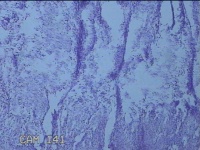

宫腔粘膜下肌瘤

性别

女

年龄

36岁

临床诊断

粘膜下肌瘤

一般病史

阴道流血42天。

标本名称

大体所见

灰白暗红色不规则组织1.3x0.5x0.2㎝一堆,切面均为灰白色结节状或编织状,质硬。